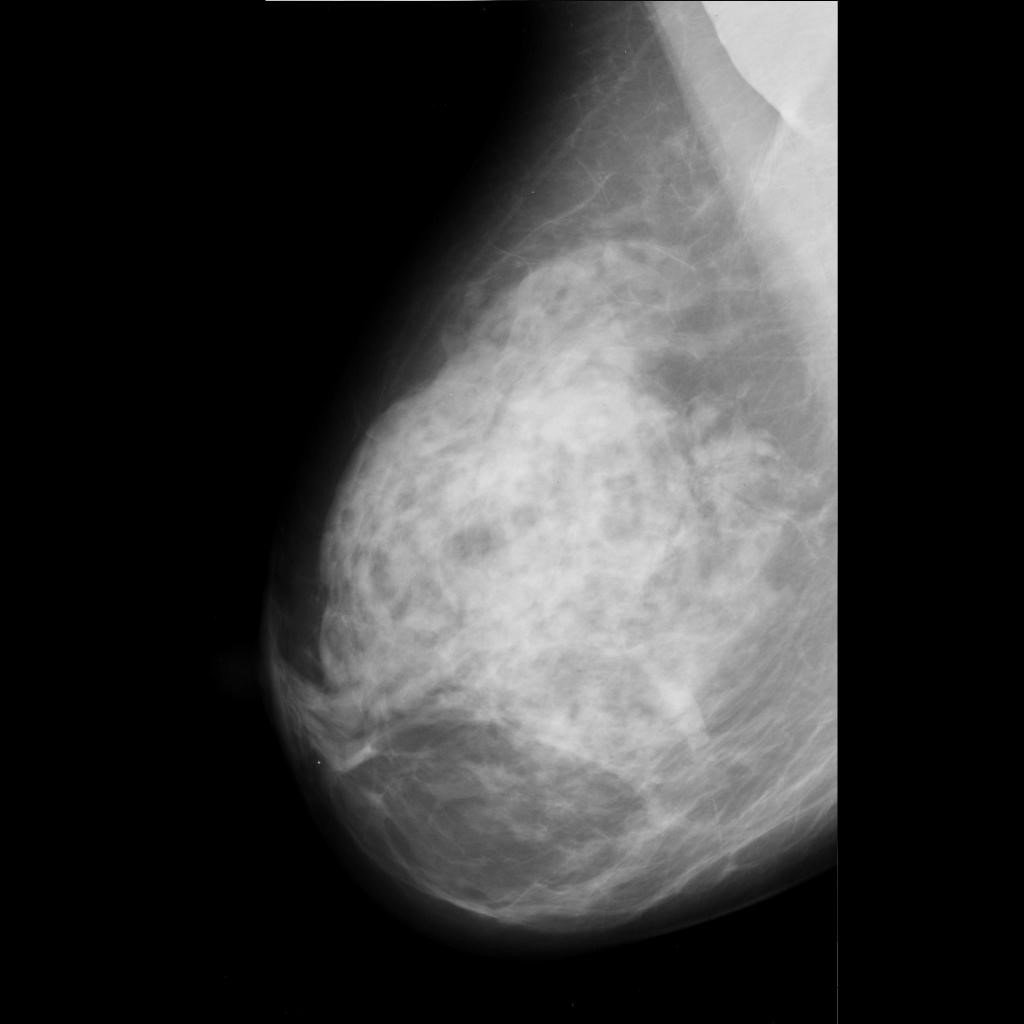

malignant